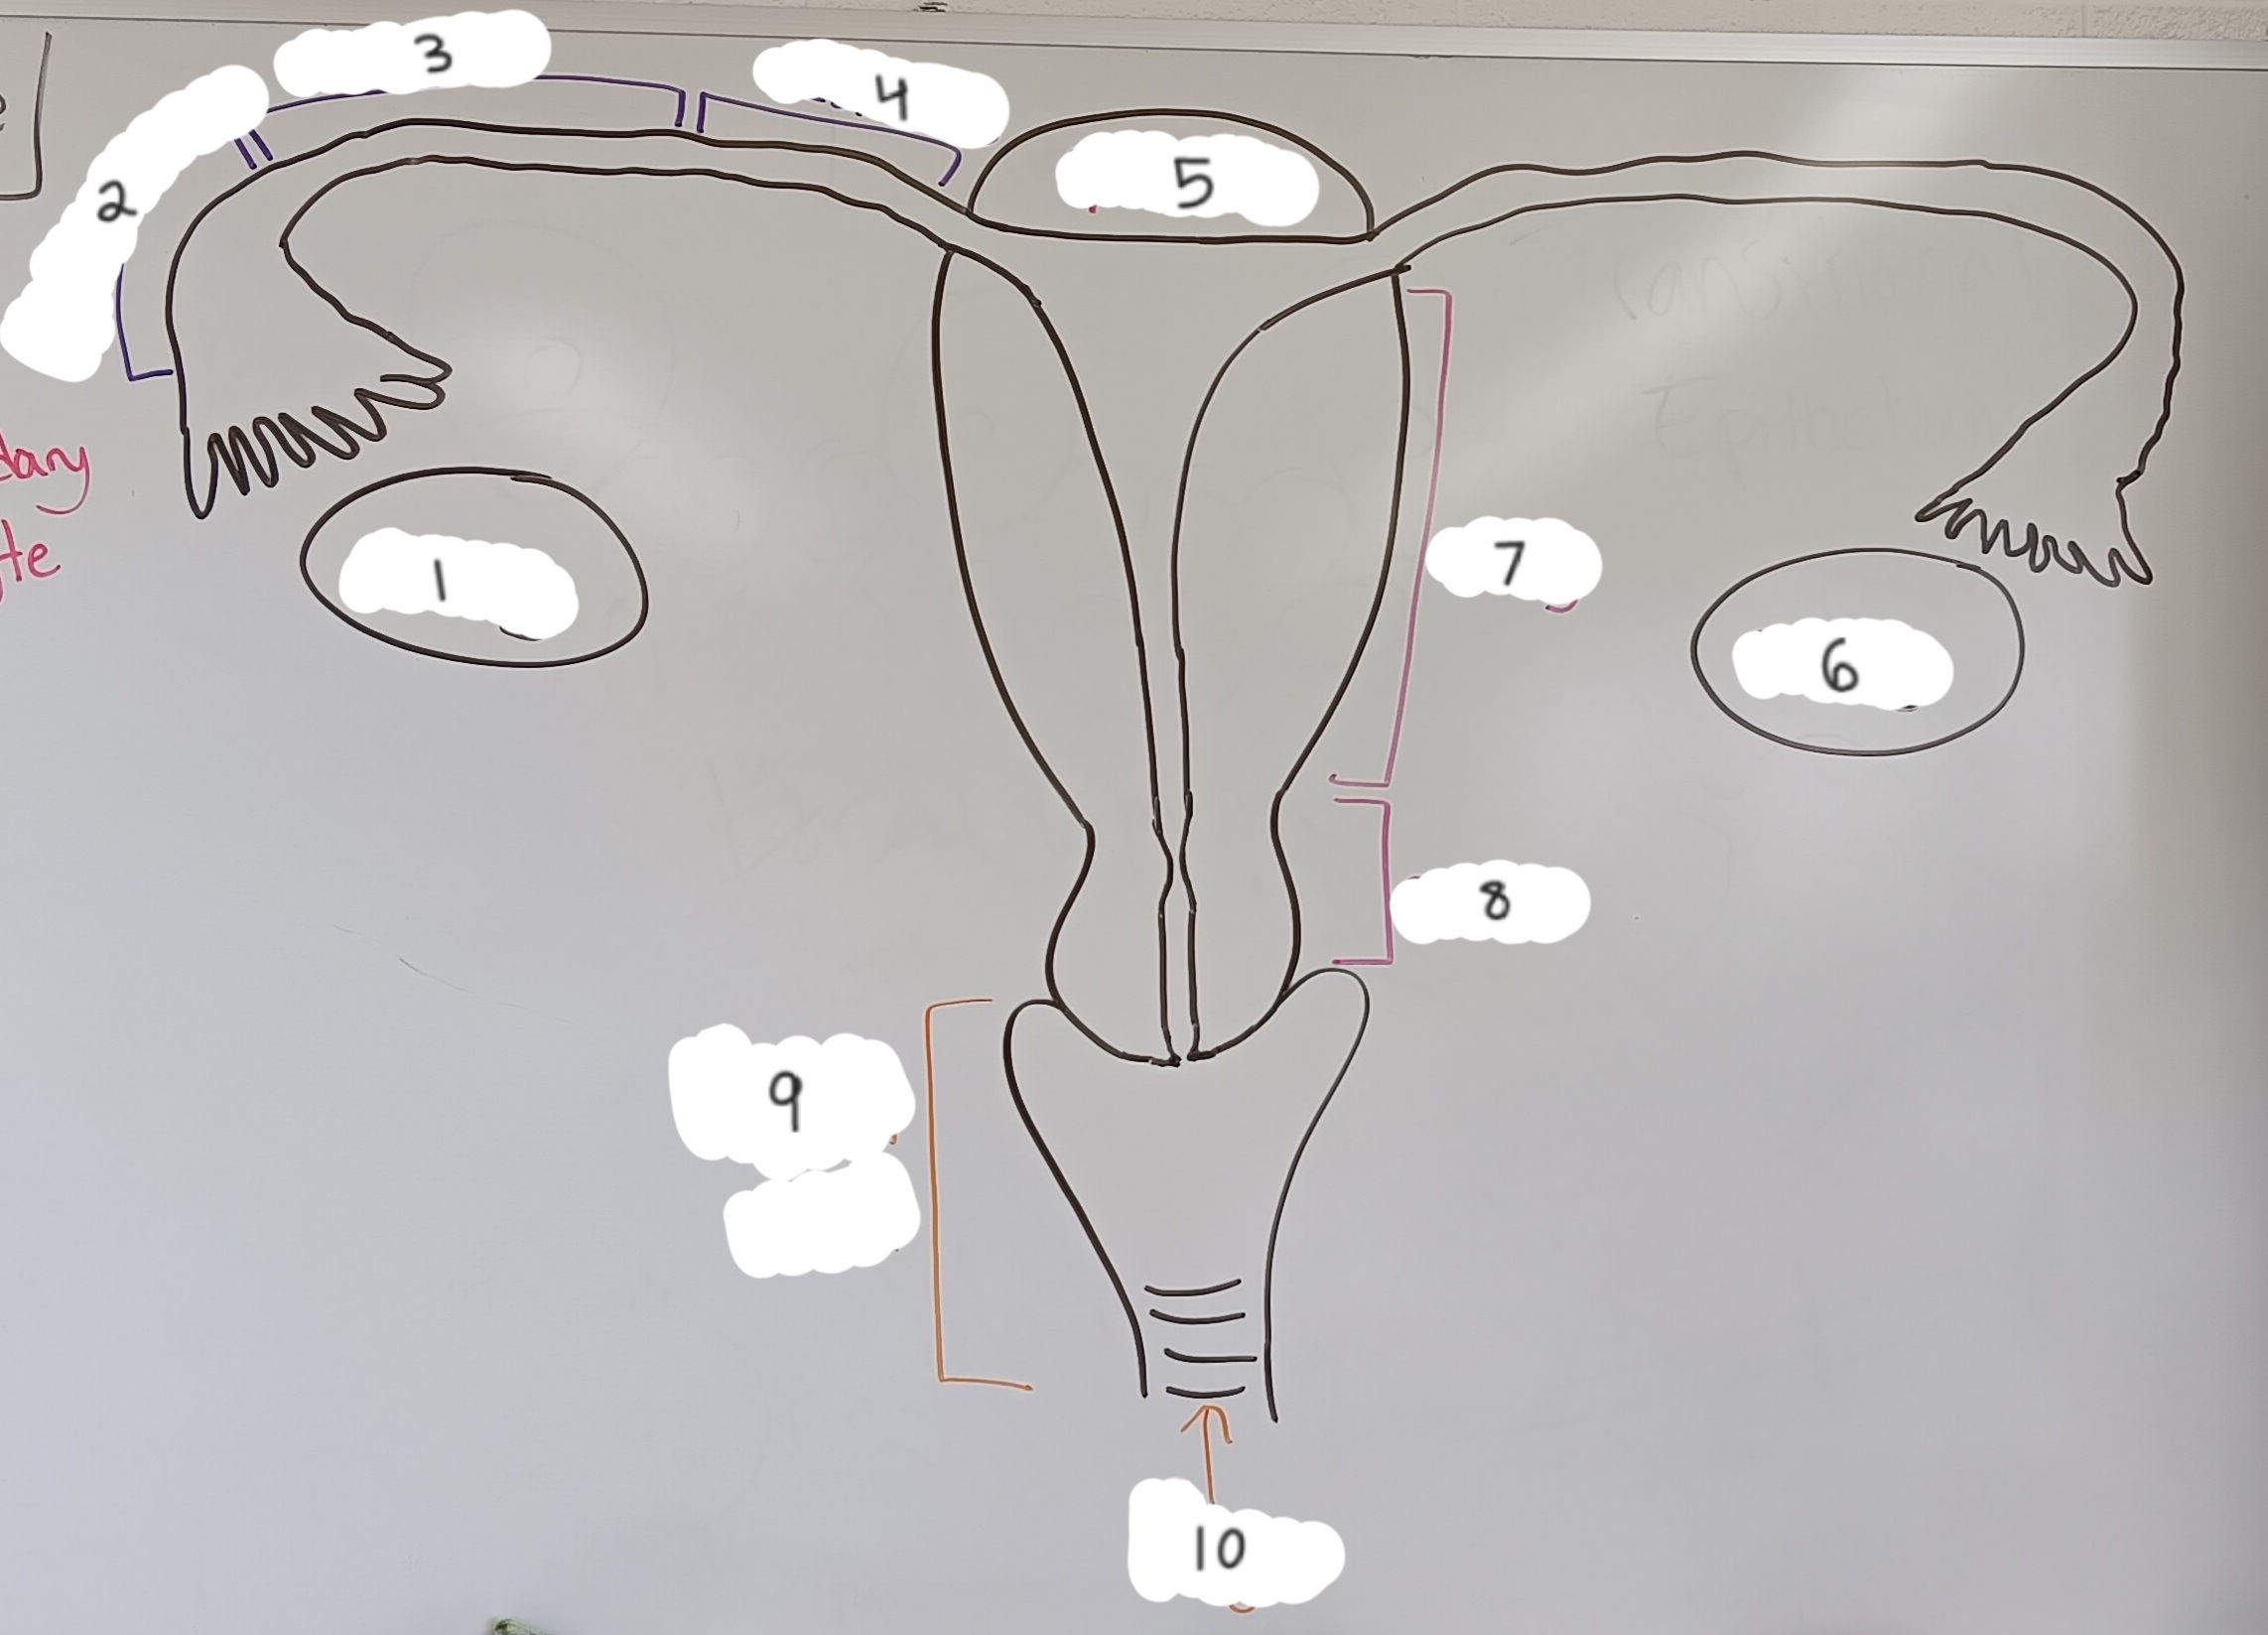

right ovary

1 (lt or rt)

infundibulum

2

ampulla

3

isthmus

4

fundus

5

Vagina

Vaginal orifice

Fallopian tube

Fimbriae

Infundibulum

Ampulla

Isthmus

Uterus

Fundus

Body of uterus

Cervix

Internal os

Cervical canal

External os

Ovary